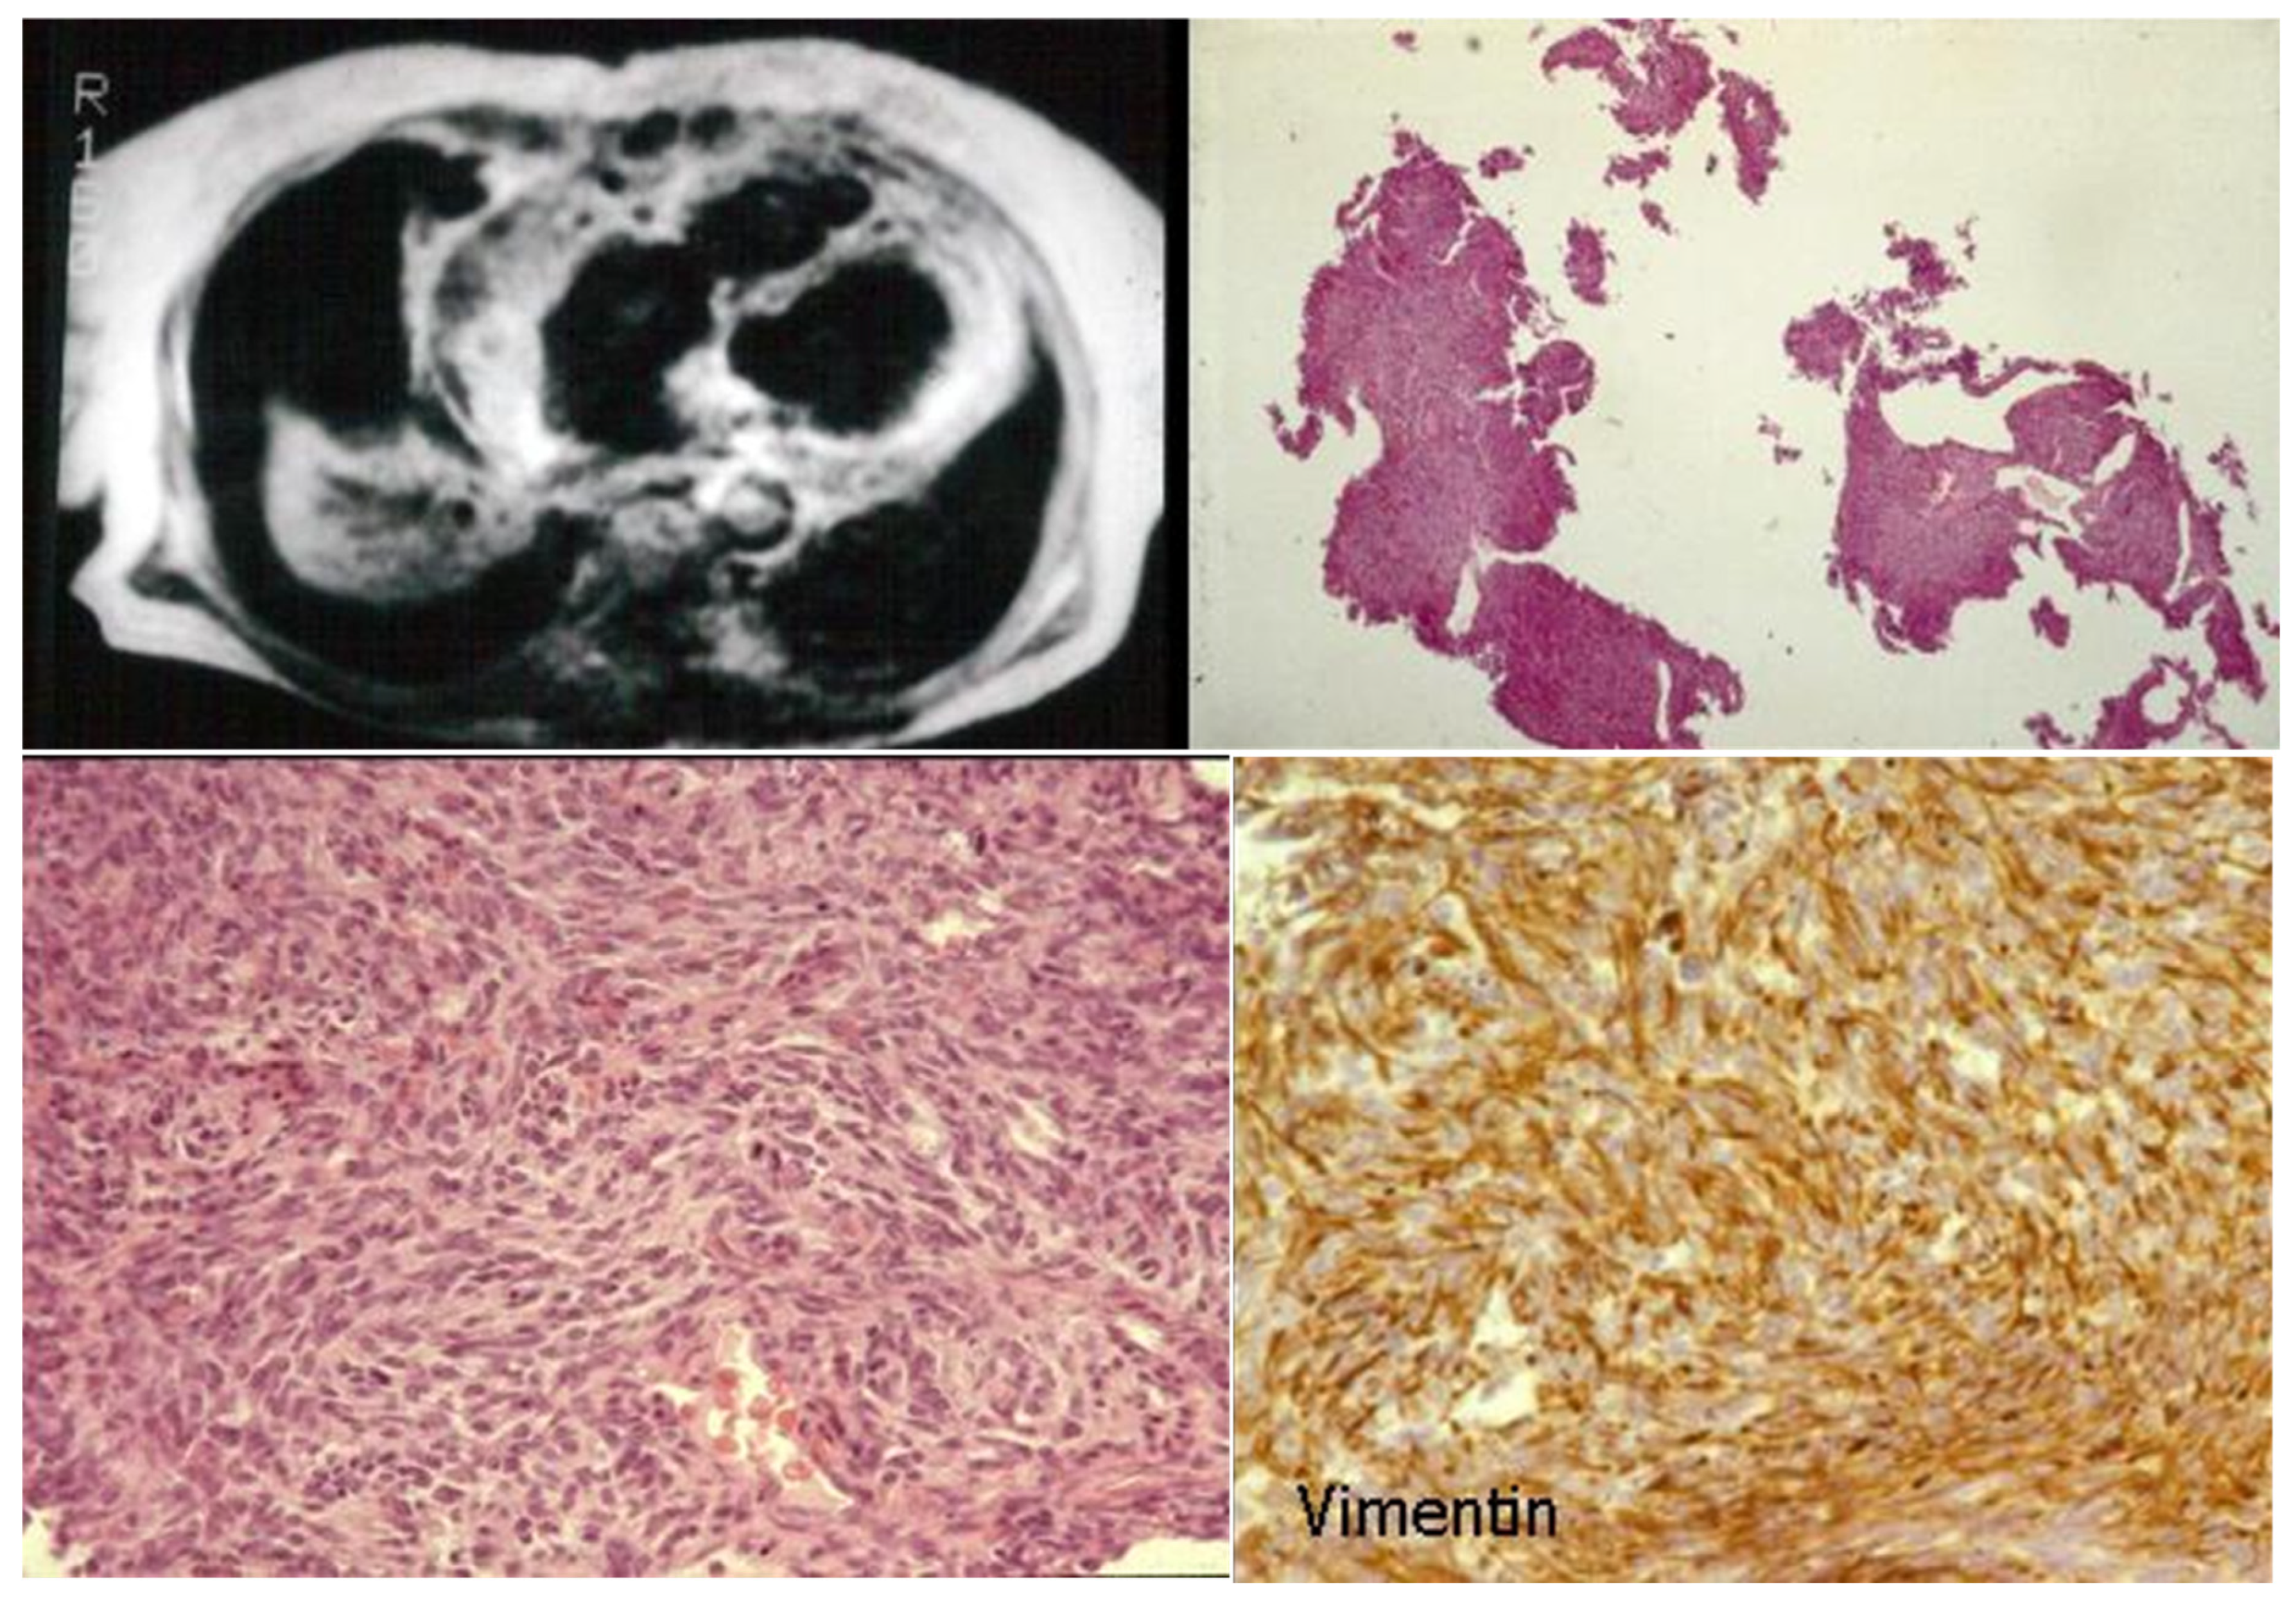

7. Clinical Indications of Endomyocardial Biopsy

- Poletti, A.; Cocco, P.; Valente, M.; Fasoli, G.; Chioin, R.; Thiene, G. In Vivo Diagnosis of Cardiac Angiosarcoma by Endomyocardial Biopsy. Cardiovasc. Pathol. 1993, 2, 89–91. [Google Scholar] [CrossRef]

- Basso, C.; Stefani, A.; Calabrese, F.; Fasoli, G.; Valente, M. Primary Right Atrial Fibrosarcoma Diagnosed by Endocardial Biopsy. Am. Heart J. 1996, 131, 399–402. [Google Scholar] [CrossRef] [PubMed]